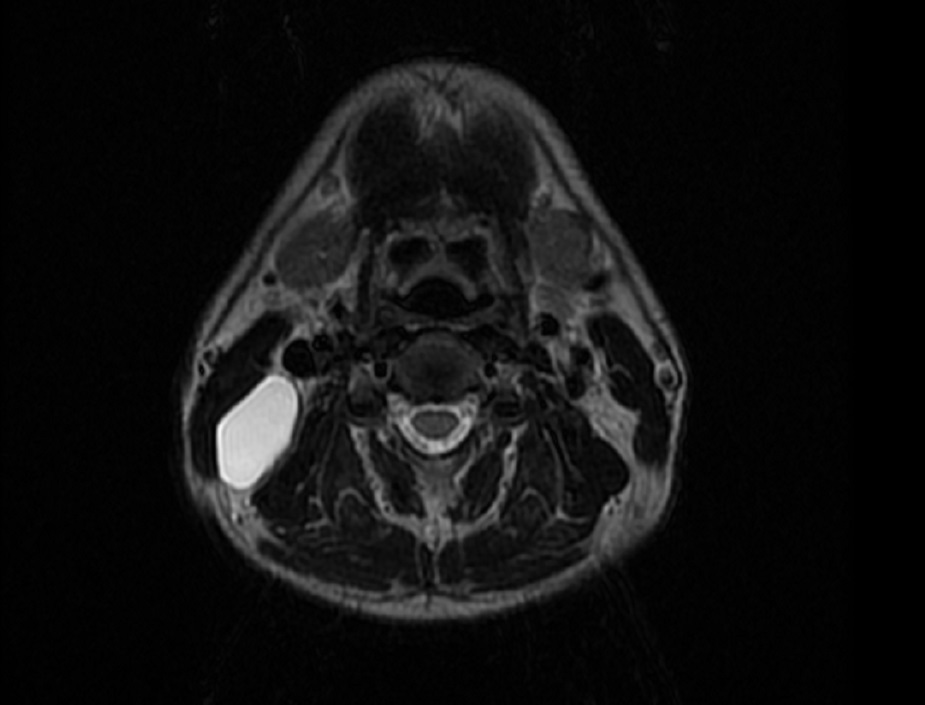

Thyroglossal duct cysts. Neck MRI – Detailed imaging of the cyst. Courtesy Dr. V. Penopoulos.